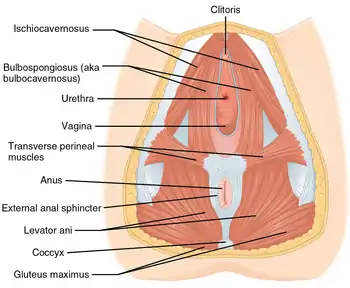

Muscles of the female perineum | |